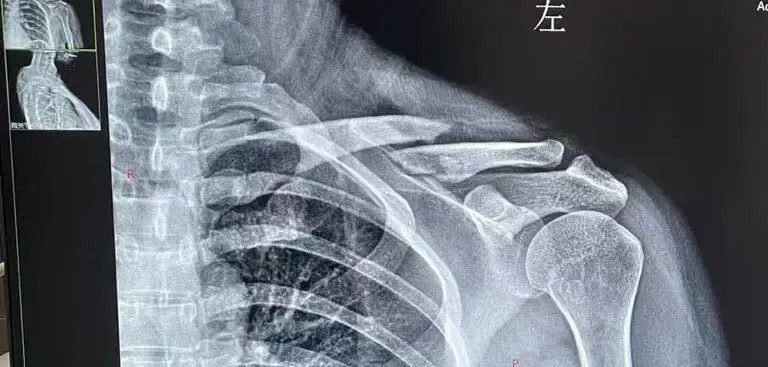

“刚处理完伤口,骨科主任赵建国便快步走来。他俯身查看我的肩部情况,一边轻柔的检查我的受伤部位,一边询问受伤细节,很快就给到我诊断意见”小丽描述着当时看诊的情况,“赵主任说我锁骨这里局部肿胀明显,大概率是锁骨骨折,得赶紧去拍个片子确认情况。 话音刚落,他就迅速到诊室给我开好了医嘱。”

跟着导诊人员做完检查,片子很快便传到了诊室的电脑上。赵主任指着片子上移位的骨折处,耐心地为小丽分析:“锁骨骨折大部分采取保守治疗,但这次的骨折确实比较严重,移位明显,保守治疗难以复位,只能优选手术治疗。另外手术的话除了将骨折复位良好,也可以让你能早期活动,避免了长时间八字绷带固定的痛苦。”